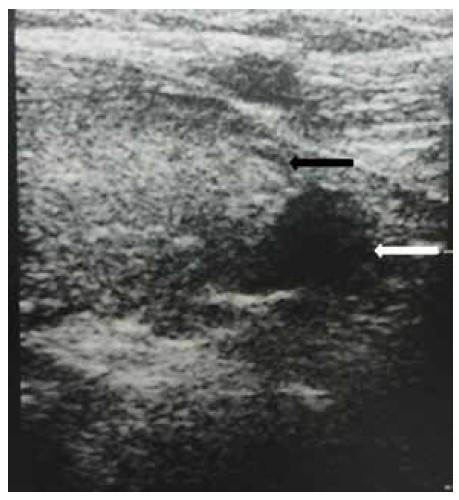

Ультразвуковое исследование органов шеи выявило увеличение размеров щитовидной железы. Ниже левой доли щитовидной железы присутствовало узловое образование (0,8 см) со значительно сниженной эхогенностью [Рис. 1]. МРТ головного мозга продемонстрировала двустороннюю кальцификацию бледного шара с симметричными гиперинтенсивными включениями на Т1- и Т2-взвешенных изображениях [Рис. 2], а также гипоинтенсивность на взвешенных по магнитной восприимчивости изображениях (SWI) [Рис. 3]. Селлярные/супраселлярные поражения либо усиления отсутствовали. Для подтверждения аутоиммунной этиологии мы провели анализ периферической крови пациентки на содержание CD4+FOXP3+Treg клеток, которое составило 2,47 при нормальном значении 6,68, что свидетельствует в пользу аутоиммунной этиологии заболевания.

Рис. 1: Ультразвуковое исследование органов шеи демонстрирует наличие гипоэхогенного узлового образования (белая стрелка) в месте предполагаемой локализации паращитовидной железы, ниже левой доли щитовидной железы (чёрная стрелка).

Неожиданной находкой в настоящем случае было узловое образование в области предполагаемой локализации паращитовидной железы, ниже левой доли щитовидной железы; образование было выявлено при ультразвуковом обследовании в связи с гиперплазией, аденомой либо инфильтрацией паращитовидной железы. Оно было расположено отдельно от нижнего края щитовидной железы и не являлось экзофитным узловым образованием щитовидной железы. Также было возможно, что узловое образование представляет собой лимфатический узел небольшого размера. Возможность для подтверждения паратиреоидного генеза узлового образования по поглощению сестамиби отсутствовала в связи с недоступностью оборудования для проведения сцинтиграфии паращитовидных желез с сестамиби. Тем не менее, на МРТ пациентки присутствовали признаки кальцификации базальных ганглиев. У пациентки отсутствовали хронические заболевания печени, а также признаки метаболических либо нейродегенеративных расстройств. Наиболее вероятной причиной развития кальцификации базальных ганглиев является эндокринная патология, вызвавшая нарушение метаболизма кальция; данная ситуация может напрямую быть связанной с тиреотоксикозом либо развиваться вторично, на фоне патологии паращитовидной железы [4,5].